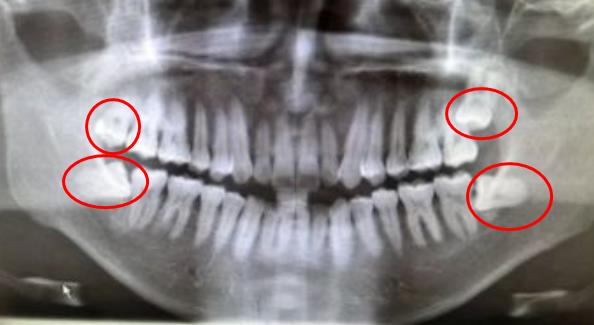

深圳牙科醫院醫生進一步解釋到,智齒是口腔內(nei) 很晚萌出的一顆牙齒,處於(yu) 口腔的較末端,從(cong) 門牙開始向後數,如果有第8顆牙齒,那麽(me) 多半是屬於(yu) 智齒。如果是經常發炎疼痛、位置不正造成鄰牙蛀牙或者自己蛀牙的,建議及時拔除比較好,否則會(hui) 繼續反複發生危害。

而臉型大小很大部分是由臉部的基本骨骼來確定的,所以即便是拔除了所有的4顆智齒,對於(yu) 麵部的影響也微乎其微。因為(wei) 拔智齒無法改變臉部骨骼的具體(ti) 情況,因此,建議大家要先了解清楚比較好。而且是否需要拔除,建議找專(zhuan) 業(ye) 口腔機構醫生檢查後判斷,畢竟如果有整牙的打算,有的情況是可以把智齒牽引出來替代壞掉的鄰牙的,所以要提前告知醫生比較好,以免拔牙後無牙可用,需要正畸後種牙的情況。